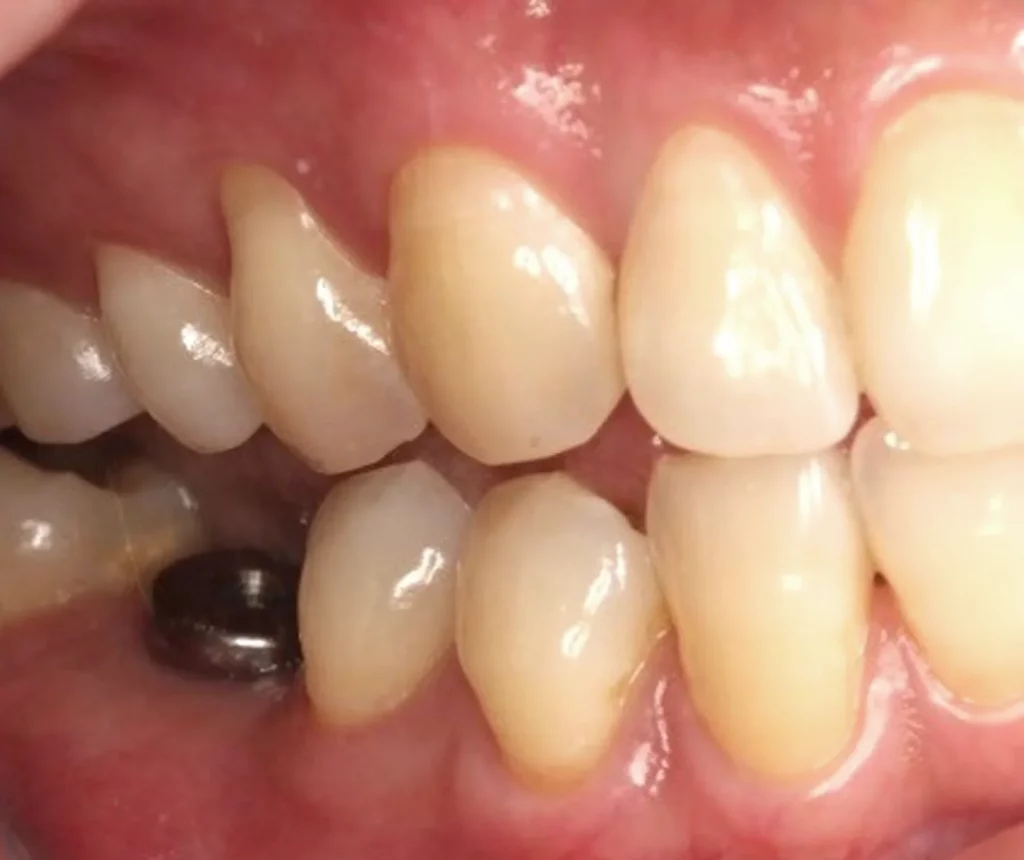

This woman had a badly broken down lower molar that had split apart and had been painfully abscessing for months. Unfortunately, it was beyond saving, and it was extracted. Keen to have the space restored, the patient opted to have an implant placed.

Below shows the crown fitted on to the implant post.